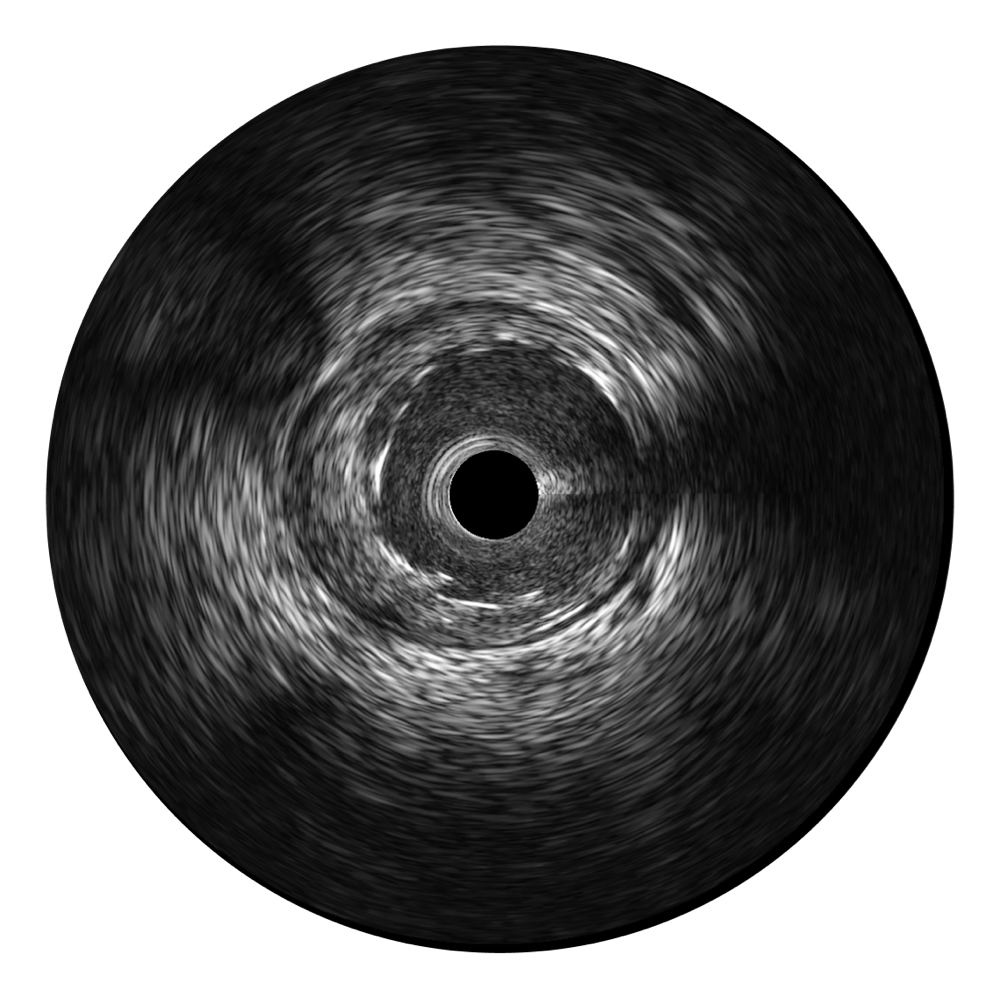

• 传统IVUS图像

对比传统IVUS导管成像,米兰官方网站宽频IVUS图像的近场支架梁显影更细腻,远场中膜外血管仍清晰可辨,兼顾远中近,兼顾分辨力与穿透深度